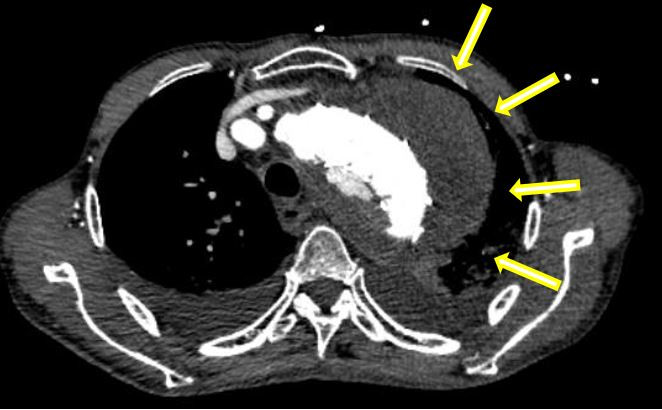

在患者轉(zhuǎn)運(yùn)過程中,血管外科急診團(tuán)隊(duì)、影像科、麻醉科、胸心外科、導(dǎo)管室、輸血科等相關(guān)科室已著手做好了急診相關(guān)預(yù)案。從患者的急診CTA上可以看到原有的胸主動(dòng)脈支架因血流動(dòng)力學(xué)影響,出現(xiàn)了近端Ⅰ型內(nèi)漏,大量血液經(jīng)由支架與主動(dòng)脈間的縫隙進(jìn)入假性動(dòng)脈瘤腔內(nèi),左側(cè)胸腔出現(xiàn)大量血腫,甚至出現(xiàn)了少量的心包積液。急診血常規(guī)顯示患者血紅蛋白才66g/L,顏老爺子已出現(xiàn)煩躁不安等譫妄表現(xiàn),為保障手術(shù)安全,團(tuán)隊(duì)立即聯(lián)系輸血科鄭春盛主任,有力地保障了患者術(shù)中用血。

急診手術(shù)刻不容緩,夏印主任帶領(lǐng)血管外科急診團(tuán)隊(duì)作了縝密的術(shù)前討論和詳細(xì)的手術(shù)方案制定。手術(shù)的難點(diǎn)主要聚焦在以下三點(diǎn):1、如何尋找內(nèi)漏口,填塞假性動(dòng)脈瘤瘤腔及內(nèi)漏口;2、弓部巨大假性動(dòng)脈瘤加上原有支架的影響,如何保障主動(dòng)脈弓上重要分支如鎖骨下動(dòng)脈及頸總動(dòng)脈的血供,盡力保障患者術(shù)中及術(shù)后不出現(xiàn)腦卒中意外 ;3、患者已出現(xiàn)休克早期狀態(tài),如何減少損傷,在保障安全的情況下盡快完成手術(shù)......綜合患者狀態(tài)和相關(guān)術(shù)前評(píng)估,最終決定在全麻下為患者行體外開窗技術(shù)保留弓上分支動(dòng)脈,同時(shí)栓塞隔絕假性動(dòng)脈瘤及內(nèi)漏口的TEVAR(胸主動(dòng)脈瘤腔內(nèi)修復(fù)術(shù))手術(shù)。為保障手術(shù)快速安全完成,血管外科黎成金主任醫(yī)師也緊急投入到手術(shù)之中。